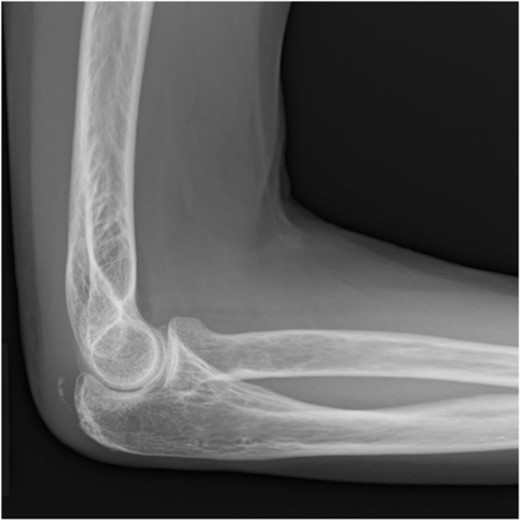

Postoperative radiography revealed reduced bone fragmentation (Fig. 5). The elbow was immobilized at 90° for 1 week postoperatively; range-of-motion exercises were started in postoperative week 2. Radiographs obtained 4 months postoperatively showed bone union (Fig. 6). At 18 months postoperatively, the patient had a range of motion of 140° flexion and 0° extension. The disability of the arm, shoulder and hand score was 0.

At 4 months after the surgery, the X-ray shows complete bone union in the lateral view.